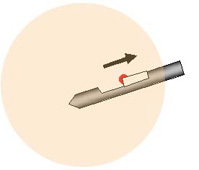

乳房をマンモグラフィで撮影し、位置決めをします。皮下と乳房に局所麻酔をします。これによりほとんど痛みを感じることはありません。病変をマンモグラフィで見ながら、乳房に針を刺入し組織を採取します。

10 分程度生検部位を押さえた後、傷口をテープで止めて完了です。縫合する必要はなく、4mm程の傷口は1~2ヶ月くらいで目立たなくなります。 当院では、位置決めにトモシンセシスを用いることにより、より正確で素早い検査を行えるようになりました。また、より快適に検査を行えるように、専用の特殊なベッドを用いて横向きに寝て検査を行なうことや、専用の椅子を用いても出来ます。

3. 切除

4. 組織の回収